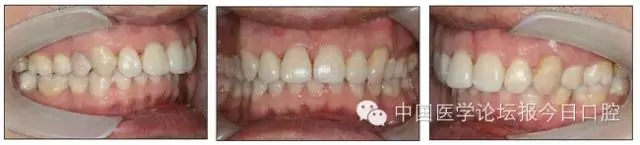

14.webp.jpg

15.webp.jpg

圖9 治療后口內(nèi)像